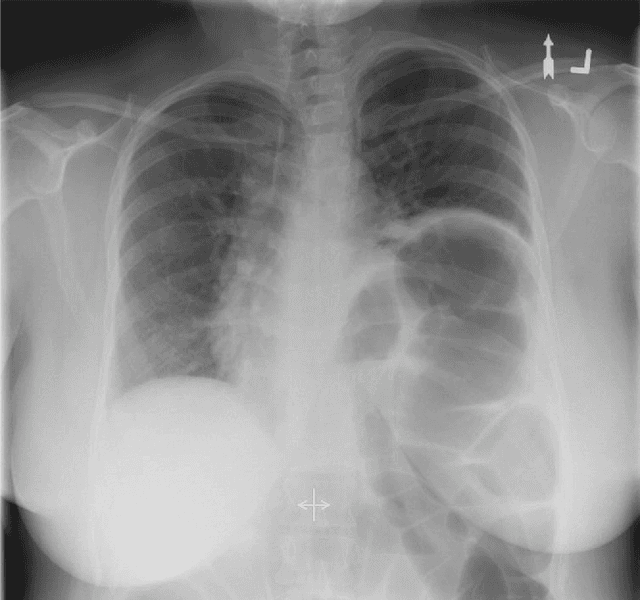

The current imaging gold standard for detecting paradoxical diaphragm motion and diagnosing hemidiaphragm paralysis is to perform the fluoroscopic sniff test. The images are visually examined by an experienced radiologist, and if one hemidiaphragm ascends while the other descends, then it is described as paradoxical motion, which is highly suggestive of hemidiaphragm paralysis. However, diagnosis can be challenging because diaphragm motion during sniffing is fast, paradoxical motion can be subtle, and the analysis is based on a 2-dimensional projection of a 3-dimensional surface. This paper presents a case of chronic left hemidiaphragm elevation that was initially reported as mild paradoxical motion on fluoroscopy. After measuring the elevations of the diaphragms and modeling their temporal correlation using Gaussian process regression, the systematic trend of the hemidiaphragmatic motion along with its stochastic properties was determined. When analyzing the trajectories of the hemidiaphragms, no statistically significant paradoxical motion was detected. This could potentially change the prognosis if the patient was to consider diaphragm plication as treatment. The presented method provides a more objective analysis of hemidiaphragm motions and can potentially improve diagnostic accuracy.